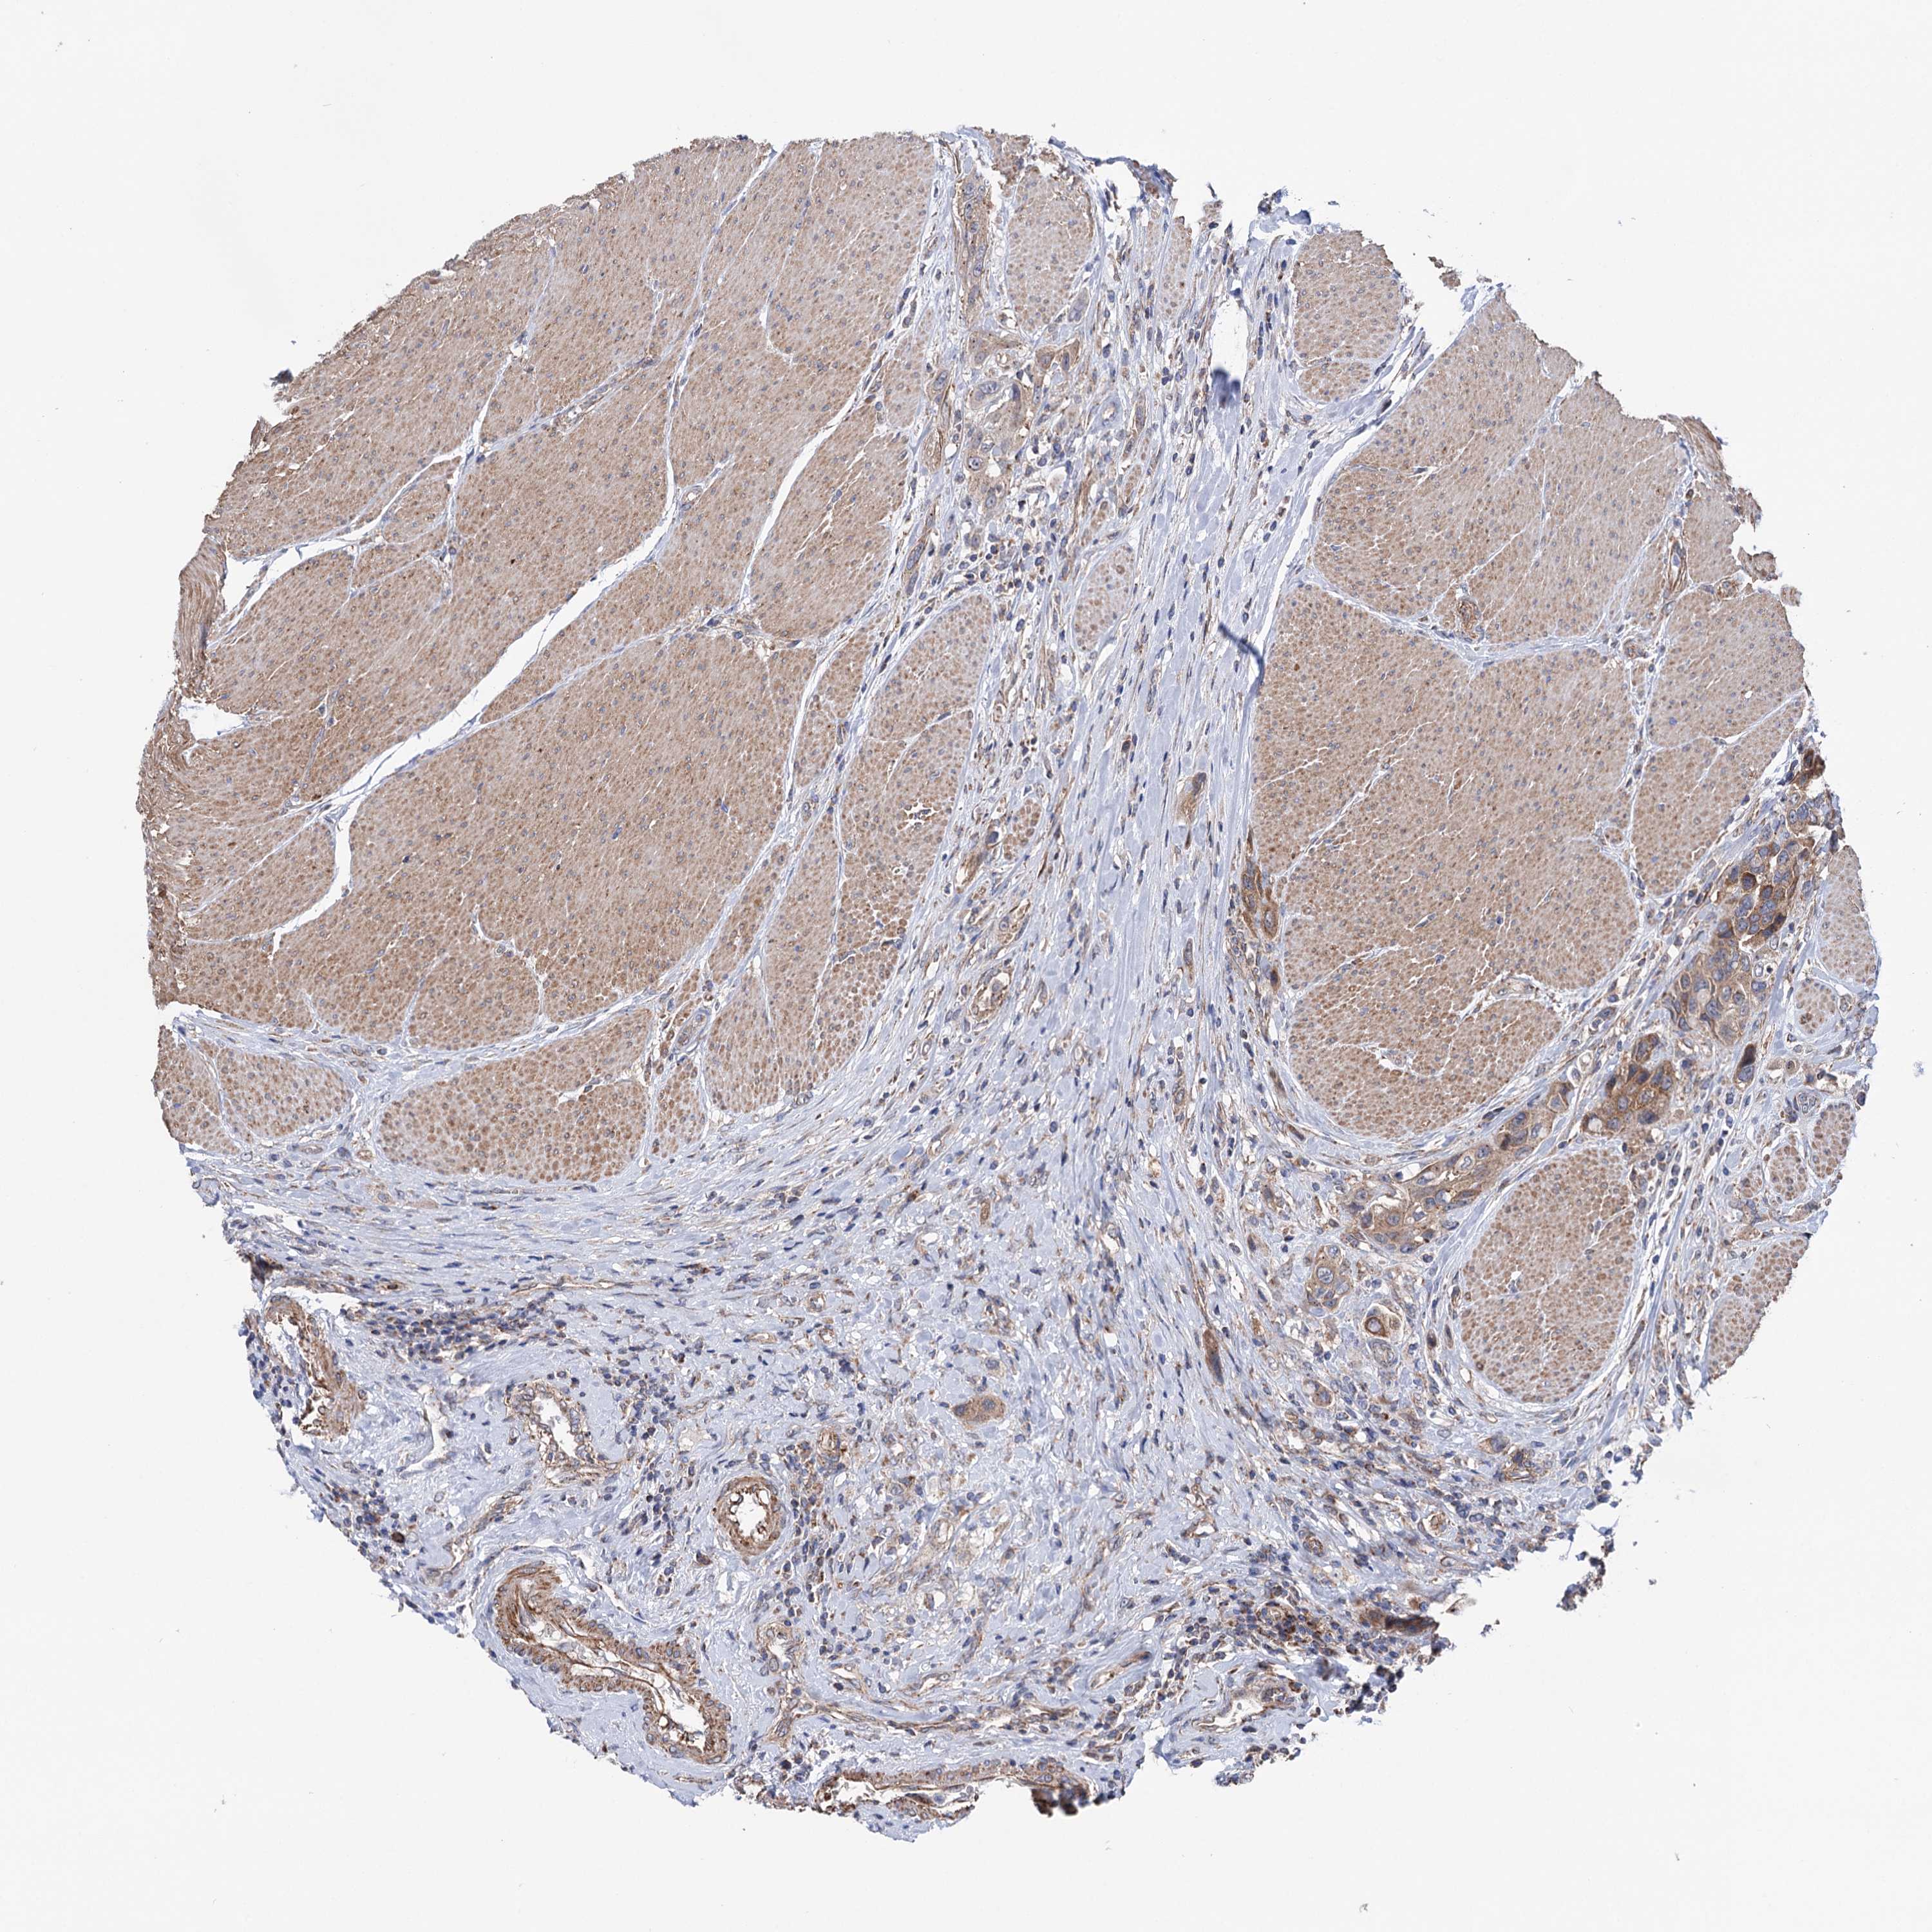

UROTHELIAL CANCER - Protein expressioni

A mouse-over function shows sample information and annotation data. Click on an image to view it in a full screen mode. Samples can be filtered based on level of antibody staining by selecting one or several of the following categories: high, medium, low and not detected. The assay and annotation is described here.

Note that samples used for immunohistochemistry by the Human Protein Atlas do not correspond to samples in the TCGA dataset.

Antibody stainingi

Antibody staining in the annotated cell types in the current human tissue is reported as not detected, low, medium, or high, based on conventional immunohistochemistry profiling in selected tissues. This score is based on the combination of the staining intensity and fraction of stained cells.

Each image is clickable and will lead to virtual microscopy that enables deeper exploration of all samples and also displays staining intensity scores, fraction scores and subcellular localization as well as patient and tissue information for each sample.

Antibody HPA039435

Antibody HPA039536

Antibody HPA061528

Staining

High

Medium

Low

Not detected

Intensity

Strong

Moderate

Weak

Negative

Quantity

>75%

75%-25%

<25%

None

Location

Nuclear

Cytoplasmic/membranous

Cytoplasmic/membranous,nuclear

Urothelial carcinoma, High grade

Urothelial carcinoma, Low grade

Urothelial carcinoma, NOS